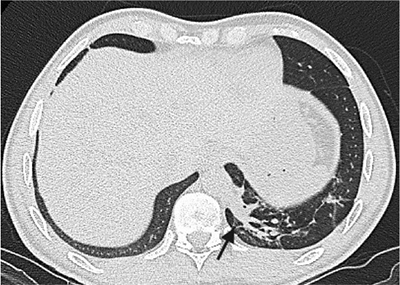

Paciente de 39 años con antecedente de Síndrome de Tolosa Hunt, quien ingresa al servicio de urgencias por disminución de la agudeza visual y cefalea. Dado el antecedente se considera realizar estudios complementarios para descartar enfermedad granulomatosa, como causa del síndrome, encontrando hallazgos incidentales en las imágenes del tórax. El secuestro pulmonar es una anomalía congénita caracterizada por tejido pulmonar displasico, sin conexión normal con la vía aérea, irrigado por la circulación arterial sistémica. Hay dos tipos de secuestros, el intralobar y el extralobar. El intralobar (75%), puede ser congénito o adquirido como secuela de infecciones recurrentes localizadas, está cubierto por pleura del pulmón normal adyacente y generalmente su drenaje venoso es a través del sistema venoso pulmonar ipsilateral. El secuestro extralobar (25%), es considerado una anomalía congénita, está revestido por su propia pleura y su drenaje venoso es sistémico. Tanto el secuestro intralobar como extralobar reciben suplencia arterial sistémica. En los estudios de imágenes, el secuestro se puede presentar como consolidación focal, nódulo o masa, de localización paravertebral, contiguo al hemidiafragma, en los lóbulos inferiores (segmento posterior), con mayor frecuencia en el lado izquierdo (98%) y con una suplencia arterial anómala dada por una o múltiples ramas (15%) generalmente de la aorta torácica y su drenaje puede ser al sistema venoso pulmonar y con menor frecuencia a la circulación sistémica.